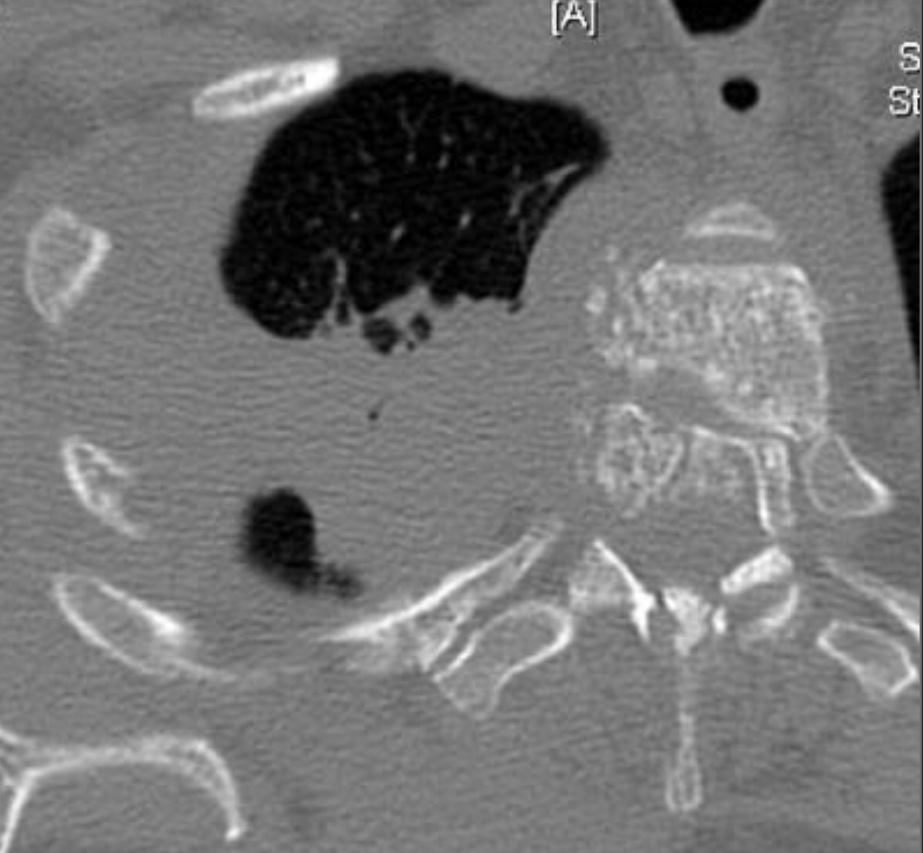

Asymptomatic pt with persistent opacity on CXR

Broncholith

should always be considered as a potential etiology when calcified intrapulmonary lymph nodes are present, particularly when they are located in the involved bronchopulmonary segment.

—Other things that can happen in bronchi:

—> soft tissue endobronchial lesion could be carcinoid

—> diffuse or segmental bronchial wall thickening could be seen in GPA/Wegener’s